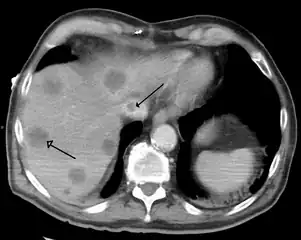

Primary biliary cirrhosis Budd–Chiari syndrome

Budd–Chiari syndrome

- Budd–Chiari syndrome is the clinical picture caused by occlusion of the hepatic vein.[19]